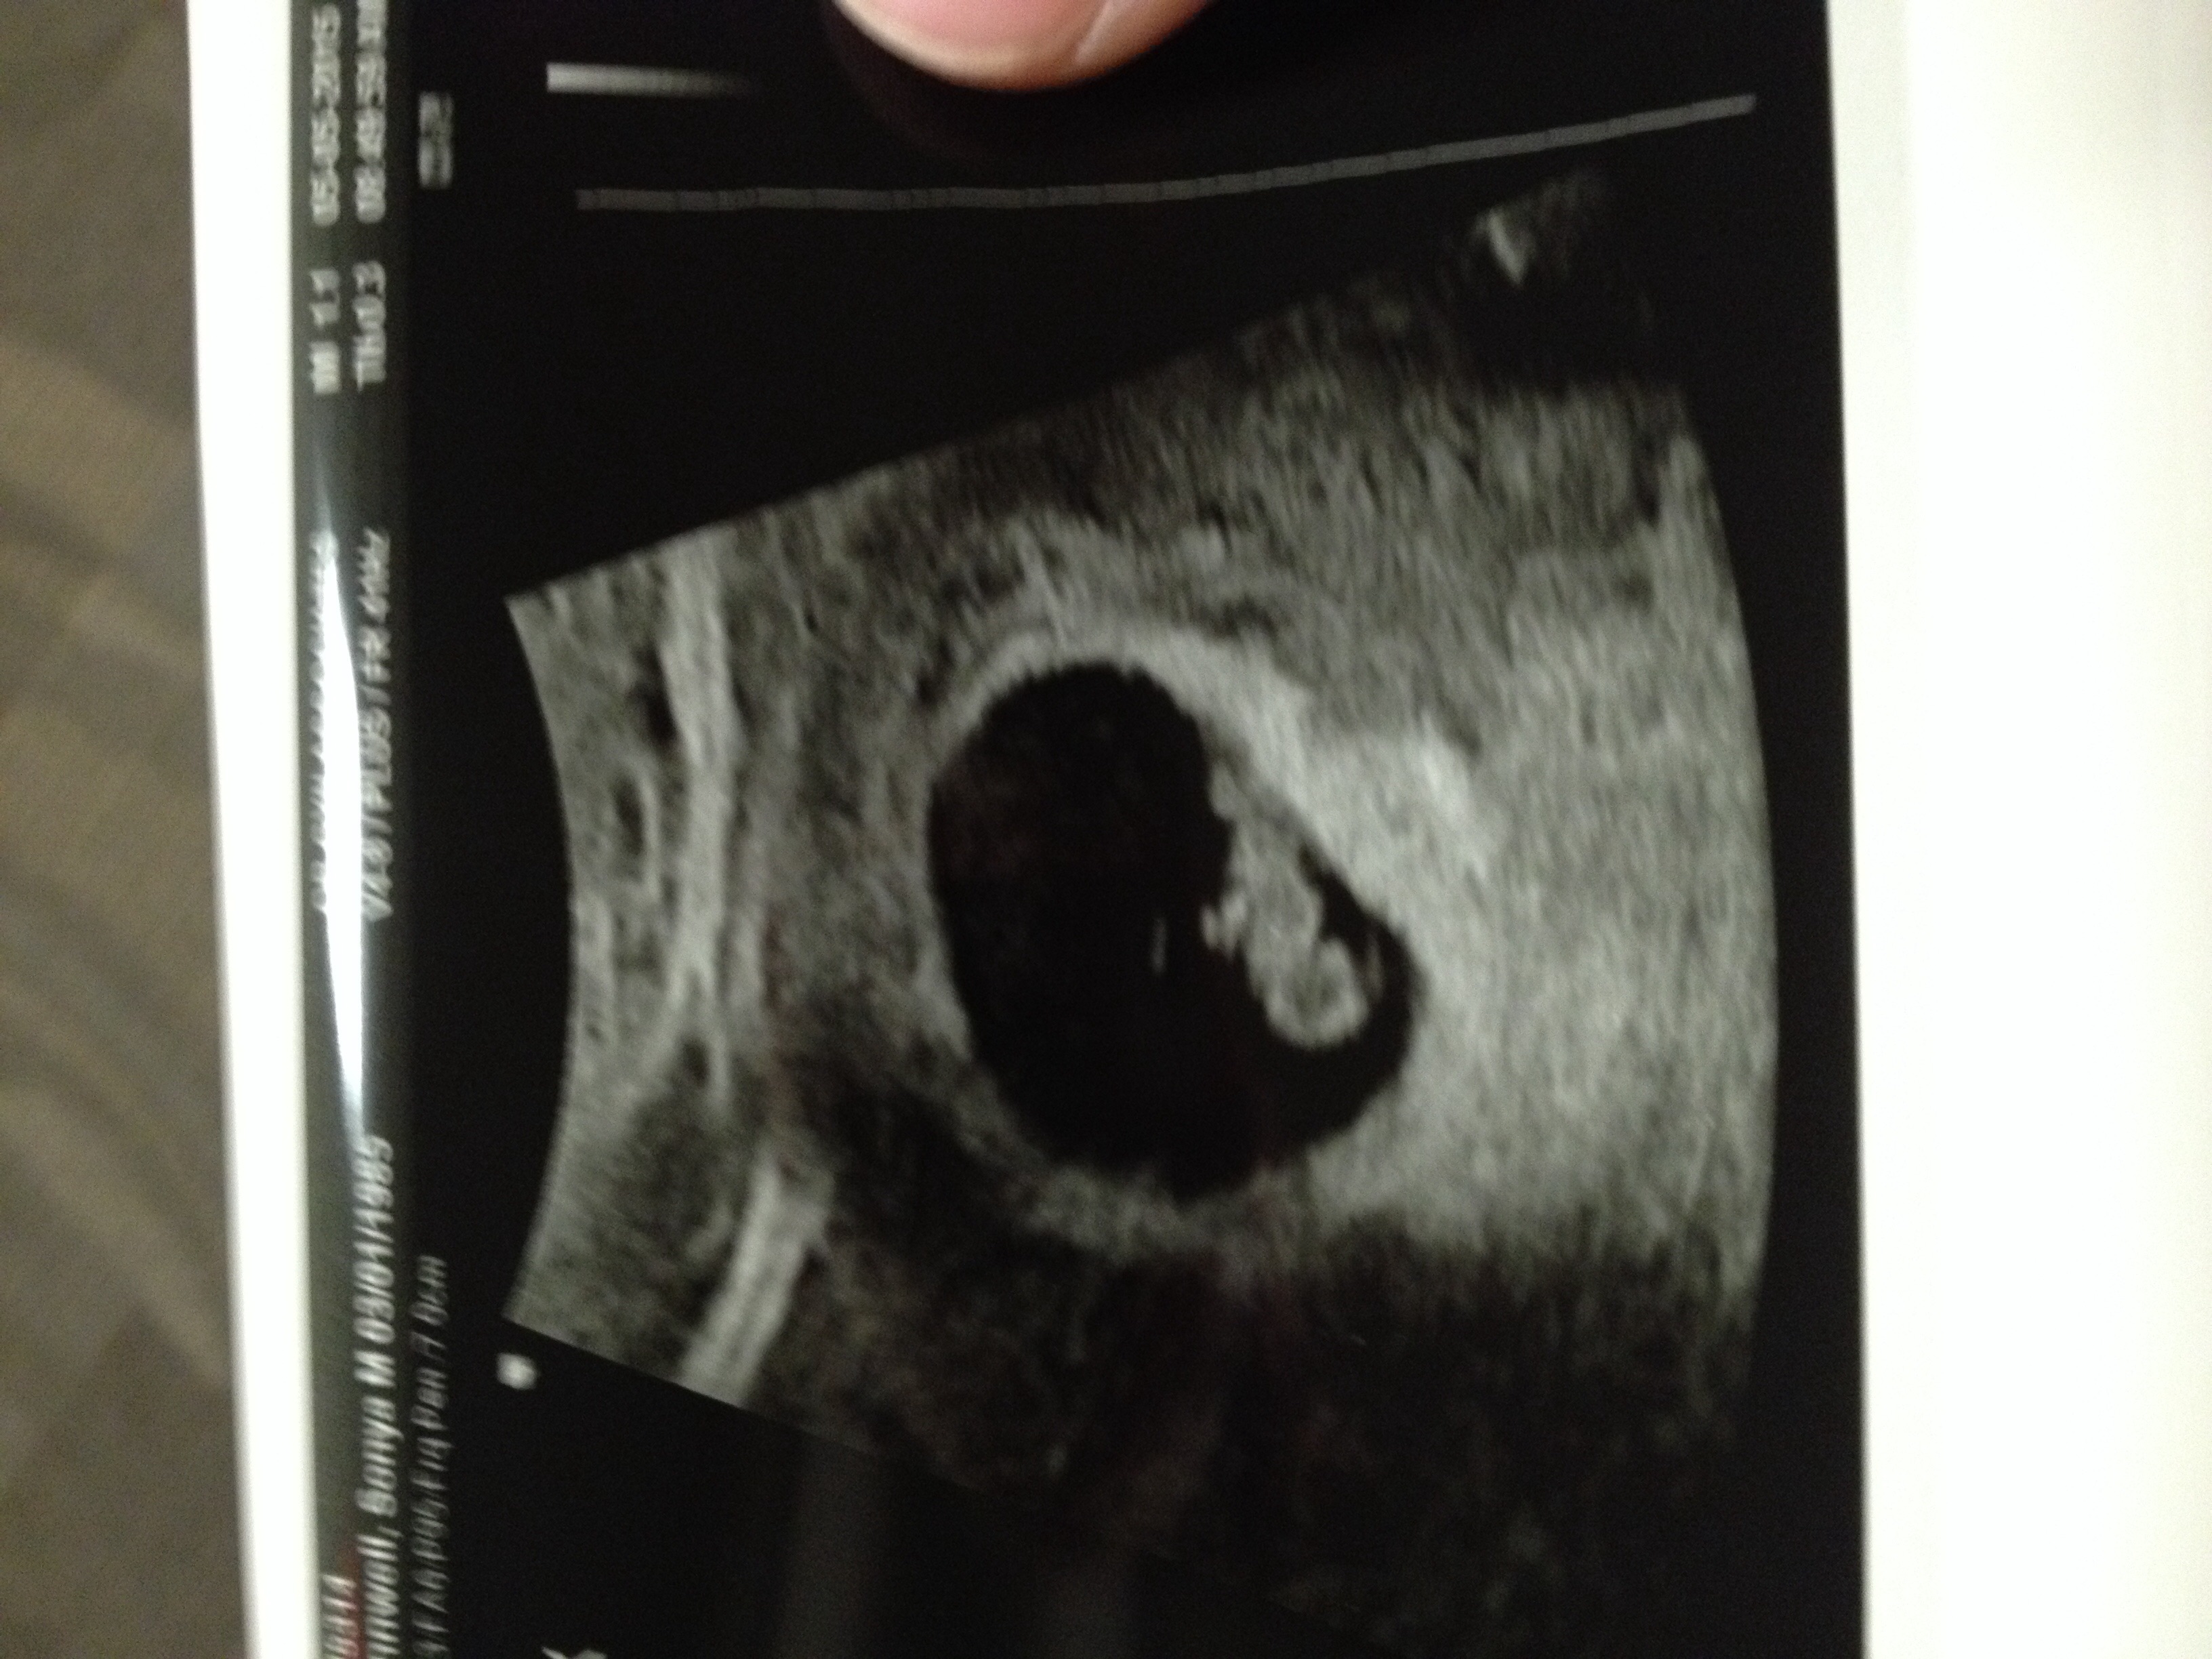

• It went great! They changed my due date to be one day earlier (why bother right), saw the baby with regular and vaginal ultrasound, able to see heart beating as well... They said everything looks perfect!

• Let's see. I'm 7w2d. I just had an ultrasound yesterday and....

• Joining this group after today's findings that I have a partially septated uterus (heart shaped, wish that was as cute as it sounds lol) and because my uterine lining is thin (only 5mm, should be at least 9mm). These things were missed on my previous pregnancy's scans and are most likely the cause of my first loss. Baby itself looked good today at 7 weeks 1 day, 127bpm but am not out of the woods yet :-/ Keeping all of you ladies in my prayers! I can't even imagine what some of you are going through, you're an amazingly strong group!

• Hey girls! It's been awhile. Things are good. Had second u/s yesterday at 8w5d. Baby looks great and hb was at 170! We saw it and heard it. Such a great sound. Still doing my shots two times a day for my clotting disorders, but honestly, I feel pretty great! Hope everyone else is hangin in there!

I am around 7w4d today (keeps changing. We had our 2nd u/s on Thursday and saw/heard a nice heartbeat of 159.5. We are released as well and I go into both my regular OBGyn and my MFM on Thursday

I am 9w6d today, but my ultrasound measured the baby at 10w1d. They aren't changing it because she said that it will vary from time to time. I was excited because the baby was measuring slightly bigger.

I didn't get to hear a heartbeat at this appointment, but we did get to see the baby and she said everything looked great. I asked her what the heart rate was and she said it looked around 140, but she didn't measure it. She did say that was right in the middle so good, but I wish she would have actually measured it. Freaks me out a little because I know around 10 weeks it averages 170. I am trying to stay focused on the fact that she said it was good and not google search anything!